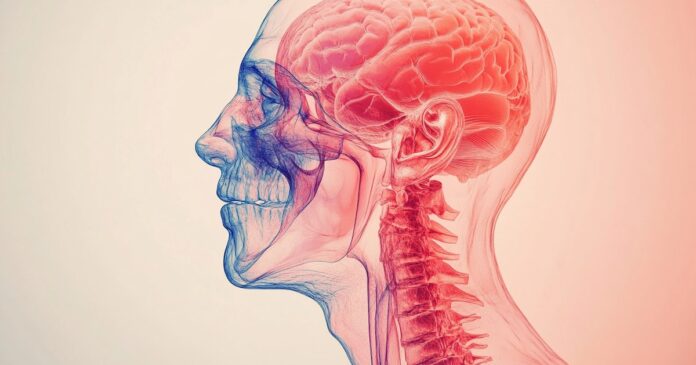

Un estudio reciente muestra que las células madre pueden reparar el daño cerebral al aumentar la formación de sinapsis y estimular la neuroplasticidad (Imagen Ilustrativa Infobae)

La zona periinfarto en el cerebro intenta compensar la pérdida de funcionalidad, pero puede alcanzar un límite en su capacidad de recuperación semanas después del accidente cerebrovascular (Imagen Ilustrativa Infobae)

El estudio muestra que las células madre pueden reparar el daño cerebral al aumentar la formación de sinapsis y estimular la neuroplasticidad (Imagen Ilustrativa Infobae)

El desequilibrio entre señales excitatorias e inhibitorias en el cerebro puede ser revertido mediante terapias basadas en células madre según nuevos hallazgos (Imagen Ilustrativa Infobae)

Las terapias celulares ofrecen esperanza a los sobrevivientes de accidentes cerebrovasculares, especialmente aquellos que enfrentan limitaciones severas en movilidad y funcionalidad cerebral (Imagen ilustrativa Infobae)